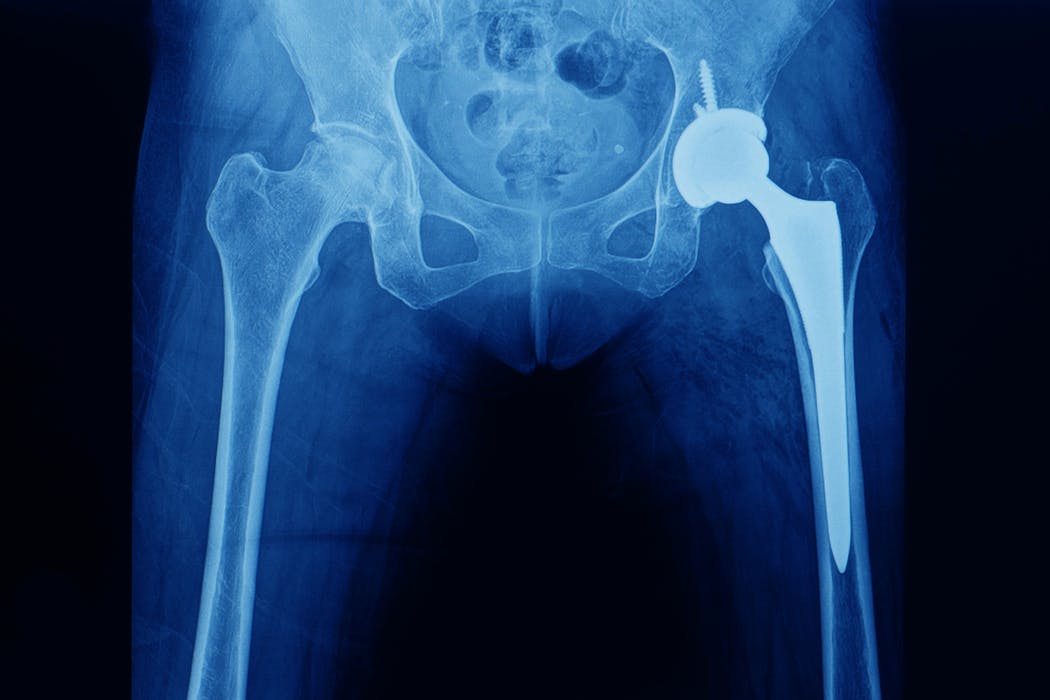

In principle, hip replacement surgery is the same operation no matter your age. But there are some slight variations.

In patients aged 70 and older, the prosthesis components are usually glued to fix them to the bone, commonly called a cemented hip. The moving parts are typically made of metal and plastic.

But in younger people, the surgeon may use implants that rely on bone growing onto the surface to fix the replacement joint in place – commonly called a cementless (or uncemented) hip. The moving part of the joint will also be separate to the part that fixes onto the bone. This means they can easily be changed if they become very worn over the years without having to change the whole joint replacement.

In younger people, the moving parts may also be made of different materials – such as ceramic, as it’s more hard-wearing than metal.